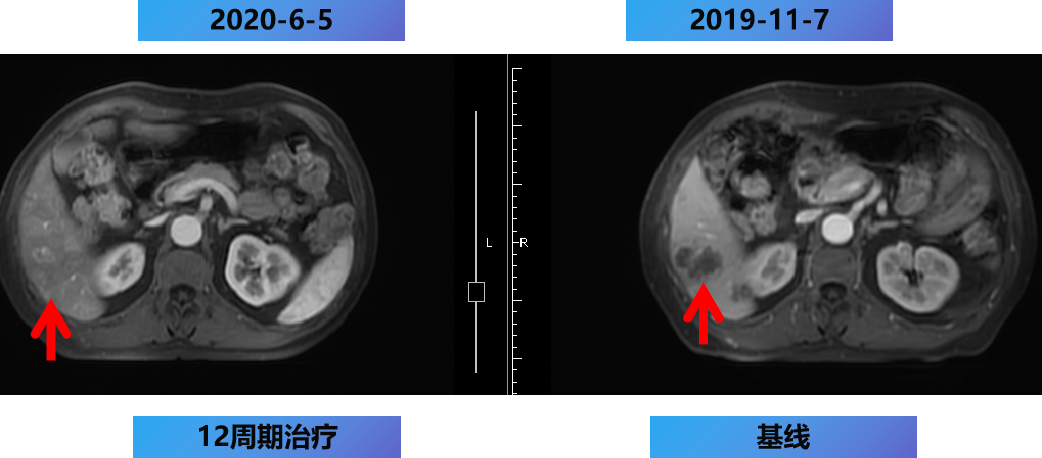

一线第1-12周期 CET+FOLFOX。

开始时间:2019-11-15至2020-5-2 每2周 一线治疗。

【治疗方案疗效评估】

MDT意见:肝转移灶可切除,肺转移灶缩小。

治疗目标:NED。

治疗策略:原发灶切除和肝转移灶切除,肺转移灶择期手术。

2020-6-8 行腹腔镜肝转移瘤切除+乙状结肠癌根治术。

术后病理示:(乙状)结肠溃疡型中分化腺癌,肿瘤大小为3cm×2.5cm×1.5cm。癌组织侵及浆膜外层。上、下切缘未见癌。肠周淋巴结见转移癌(1/16)。切除部分肝组织可见转移癌,肿瘤大小分别为3.5cm×2cm×1.6cm,2.7cm×1.5cm×1.3cm。癌组织未侵犯肝被膜,肝实质断端未见癌。